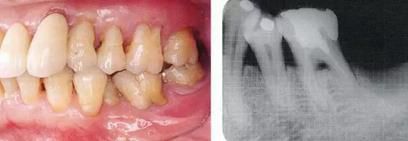

360截圖20170422101744009.jpg

▲圖5-1,2

▲圖5-1 左下5舌側(cè)移位,頰系帶高位附著,附著齦不足,口腔前庭狹小,左下6根分叉病變,左下7擴(kuò)散性骨組織吸收深達(dá)根尖部等,存在非常多的問(wèn)題。

▲圖5-2 確認(rèn)左下7骨組織吸收深達(dá)根尖部,初期治療時(shí)拔除。將左下7拔除后的X光片。